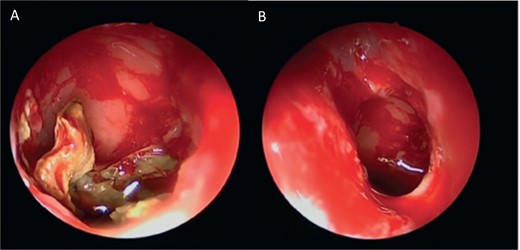

Intra-operative endoscopic view showing invasive fungal granuloma in the right maxillary sinus.

An 18-year-old adolescent mentally challenged male was complaining of chronic right thick purulent nasal discharge, cough, and headache, which did not respond to multiple courses of oral antibiotics. Purulent discharge was seen filling the right nasal cavity and the nasopharynx during endoscopic examination. NCCT images (Fig. 7) revealed a destructive right maxillary sinus lesion. The patient underwent endoscopic sinus surgery, intra-operative frozen section showed granuloma, right medial maxillectomy with removal of the invasive fungal granuloma was performed (Fig. 8), and tissue cultures revealed Aspergillus flavus. Infectious disease team was involved, and the patient was started on a 6-months course of oral antifungal agent. The patient remained symptomless throughout his 1 year regular appointments.